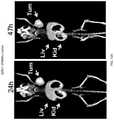

FIG. 16A shows PET/CT scan images of mice harboring HPB-ALL (CD8+) tumor xenograft comparing89Zr-Df-IAB22M minibodies with human IgG1 and human IgG2 derived hinge sequences.

FIG. 17 shows PET/CT scan images comparing uptake of89Zr-Df-IAB22M γ1 EH1 in a NOD-SCID mouse with antigen-positive HPB-ALL tumor and antigen-negative Daudi tumor (right panel only).

FIG. 30 shows PET/CT scan images comparing uptake of89Zr radiolabeled IAB22 Mbs with different hinge sequences in NOD-SCID mice bearing antigen positive HPB-ALL xenografts on the left shoulder.

FIG. 31 shows a graph of biodistribution data of89Zr radiolabeled IAB22 Mbs with different hinge sequences in NOD-SCID mice bearing antigen positive HPB-ALL xenografts on the left shoulder.